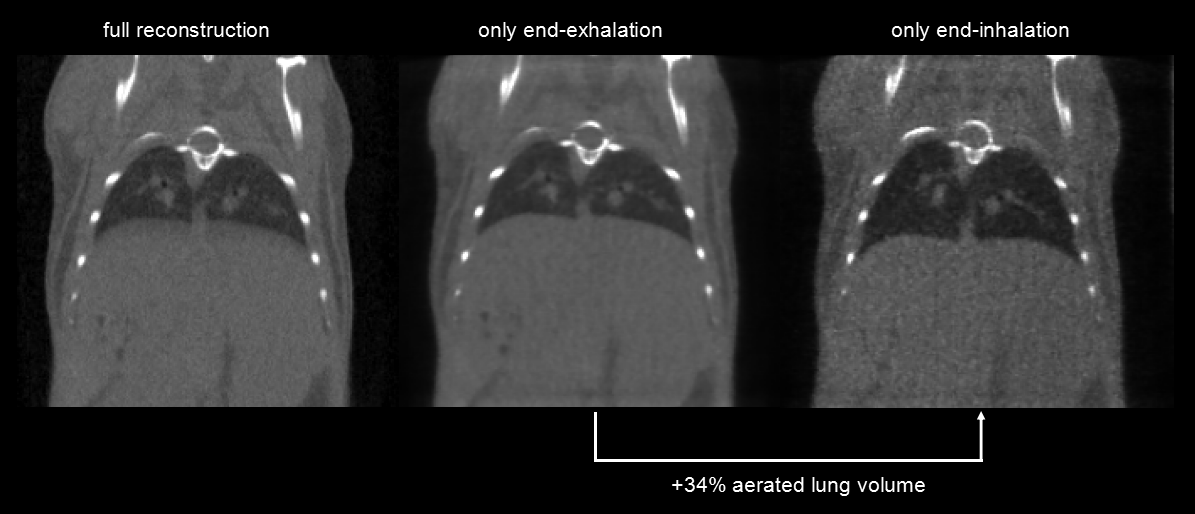

呼吸門控:超高時間分辨率(10ms),4min,390mGy。左圖:整體整合的圖。中圖:呼氣結束時的圖,右圖:吸氣結束時的圖,兩者顯示肺的容積相差34%。

圖13. 呼吸門控.png